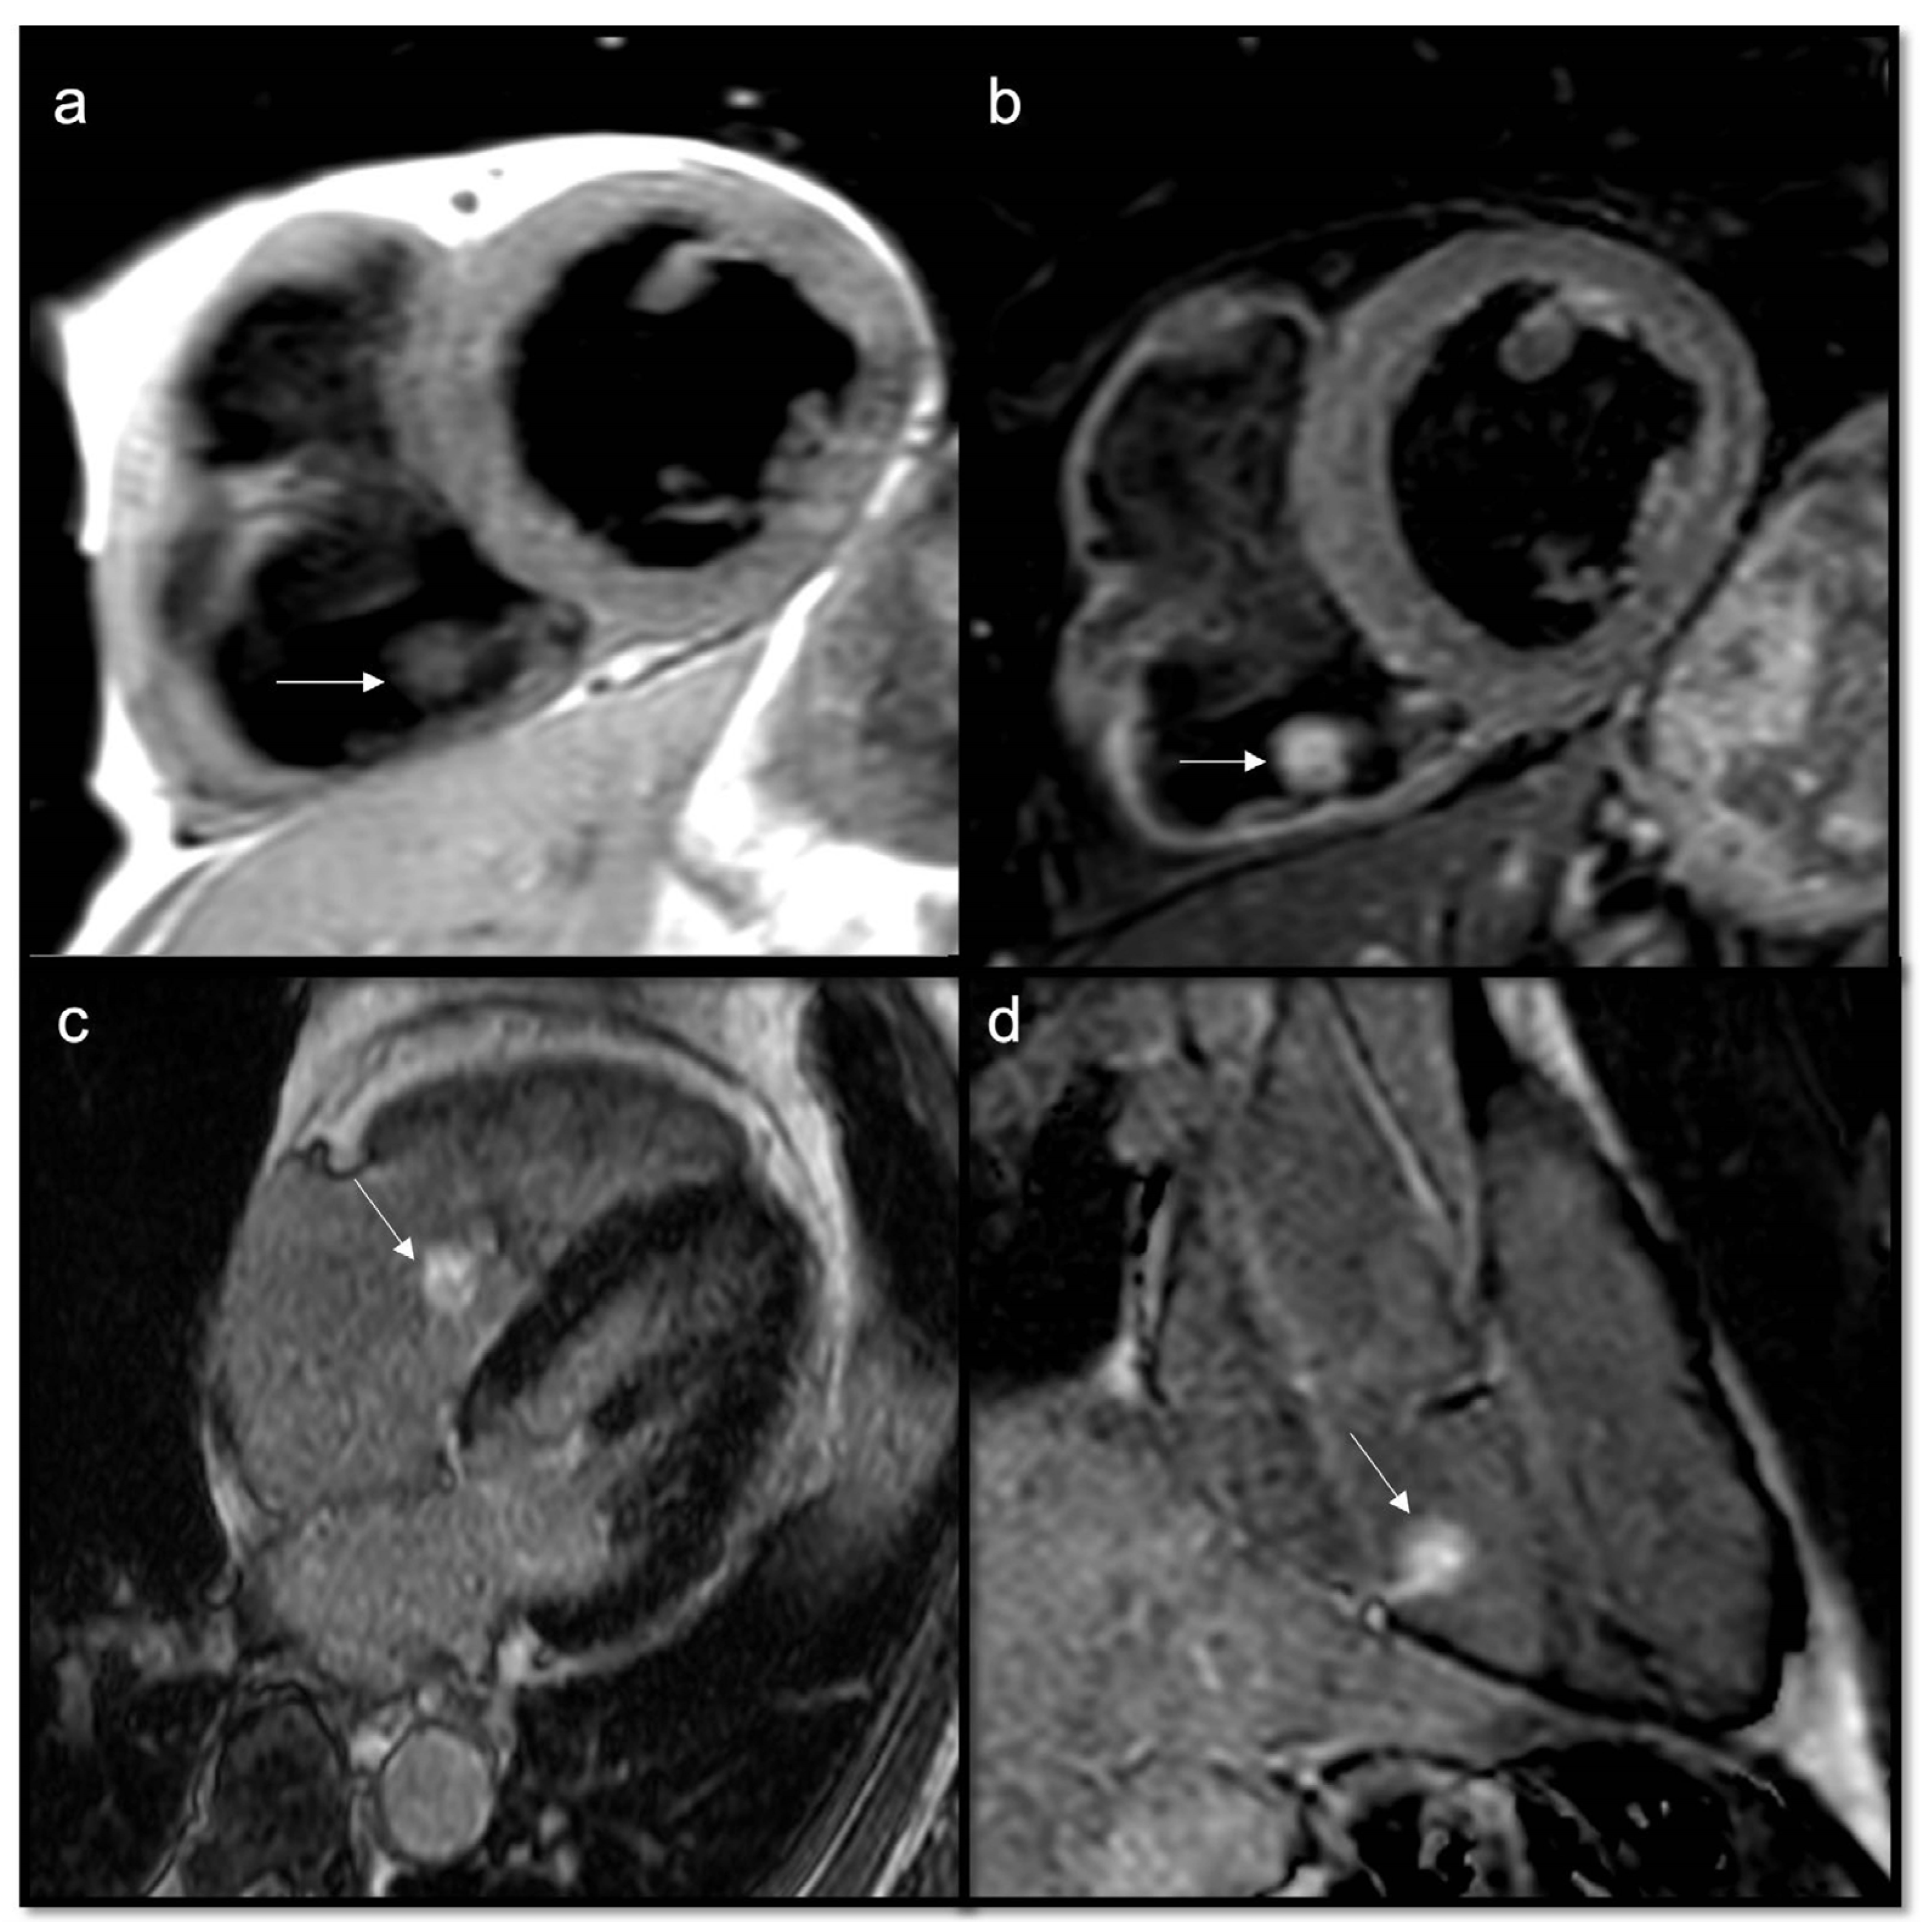

7.2.3. First-Pass Perfusion Sequences

- Assessment of vascularity

- Malignant masses often show heterogeneous enhancement; typically, angiosarcoma shows early avid enhancement as it is richly vascularized.

- Trombi due to their avascular nature appear non-enhanced.

7.2.4. Early Gadolinium Enhancement (EGE)

- Organized thrombi may show peripheral enhancement on LGE images, owing to their fibrous content.